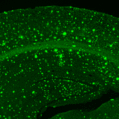

Sitemap > Presse & Kommunikation > Pressemitteilungen > Fortschreiten der Alzheimer-Erkrankung an einzelnen Neuronen zu sehen > Gehirn einer Alzheimer-Maus mit Amyloid-Plaques - Bild: Christine Grienberger / TUM

Gehirn einer Alzheimer-Maus mit Amyloid-Plaques - Bild: Christine Grienberger / TUM